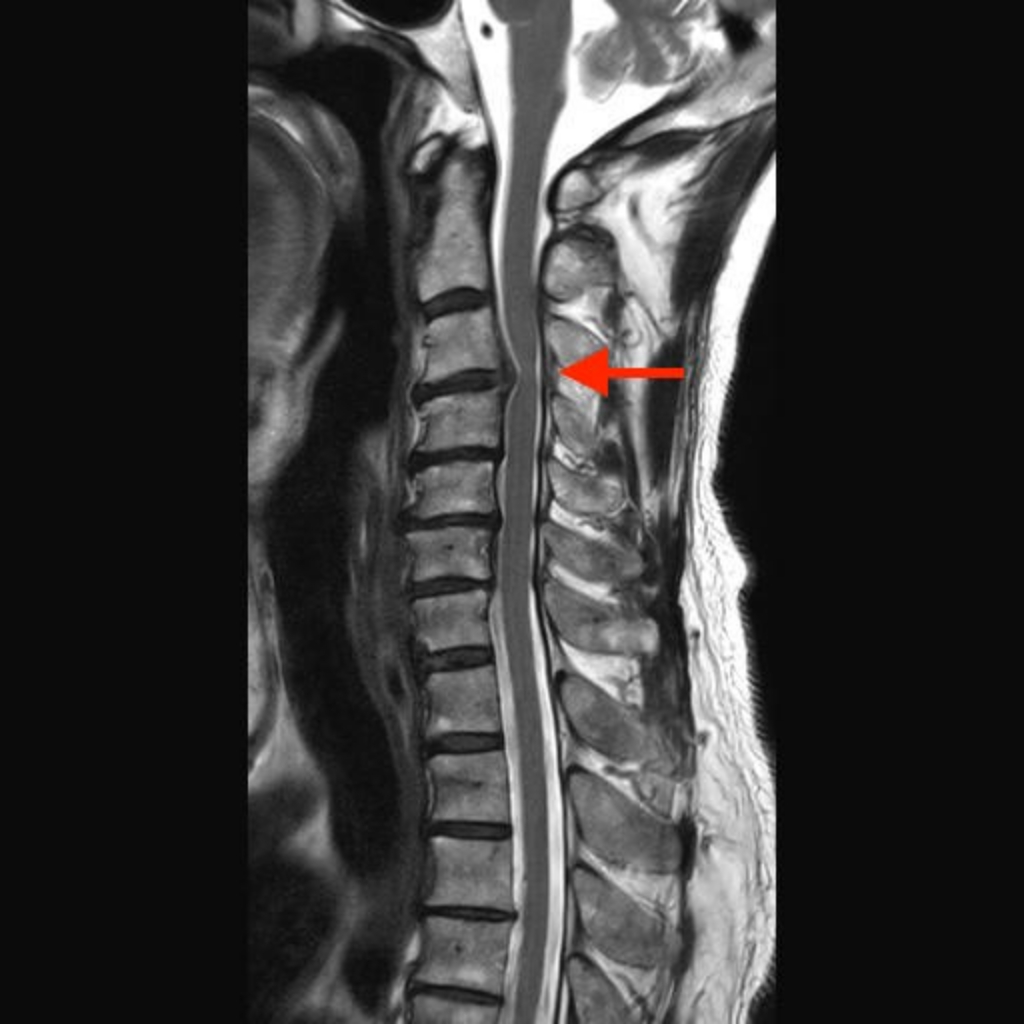

醫師能夠提供的服務,最重要的是診斷 : 頸椎狹窄的病因有許多,從發生率最高的椎間盤突出(俗稱骨刺)(圖2)、亞洲人(日本、韓國、台灣) 較常發生的後縱韌帶鈣化、到惡性腫瘤骨轉移(常見的攝護腺癌、肺癌、乳癌)(圖3)都有可能。從最基本的頸部X光到精密的核磁共振,醫師會依照症狀選擇合適的診斷工具。